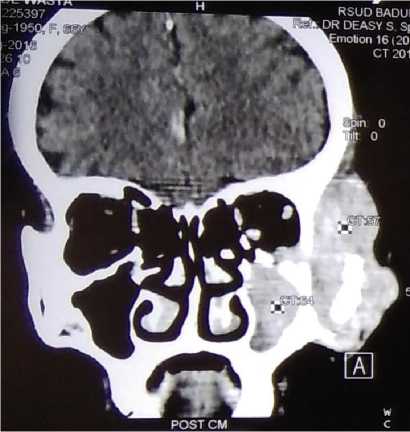

The skull X-ray was obtained, which showed the left maxillofacial bone became more blastic and thinner. We proceeded with contrast-enhanced CT scan which revealed solid mass at the left maxillofacial bone which infiltrating to left facial-buccal area, left maxillary sinus and left orbit, with bone destruction (Figure 1 and Figure 2). There was no infiltration to the intracranial area. There was no extranodal involvement of the lung, pleura, and liver.

Figure 2. Head CT coronal view.